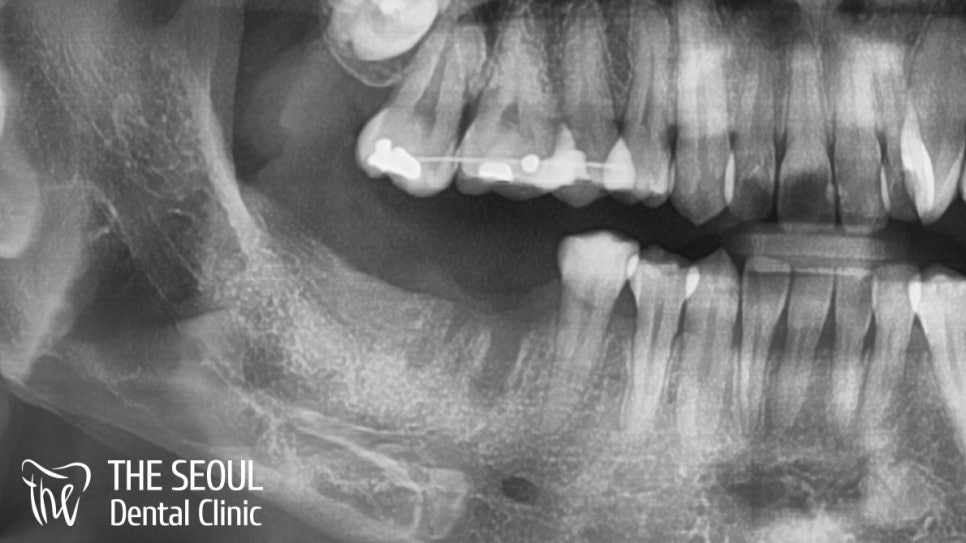

우선 상태가 어떤지 직접 확인을 해야겠죠?

외국인 치과 에서 환자의 구내를 살펴보니

오른쪽 어금니 두 곳이 빠진 채로 남아있었습니다.

아직 발치와가 아물지 않은 정도였기에

뽑은지 오래 지나지 않았음을 알 수 있네요.

엑스레이를 살펴보니 별다른 염증 반응이나

치조골 흡수 등은 일어나지 않았습니다.

다행히 원하던 대로 임플란트를 심을 수 있겠군요.